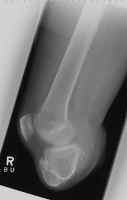

The images shown demonstrates a BKA of acceptable length. The patient is

wearing a prosthesis.